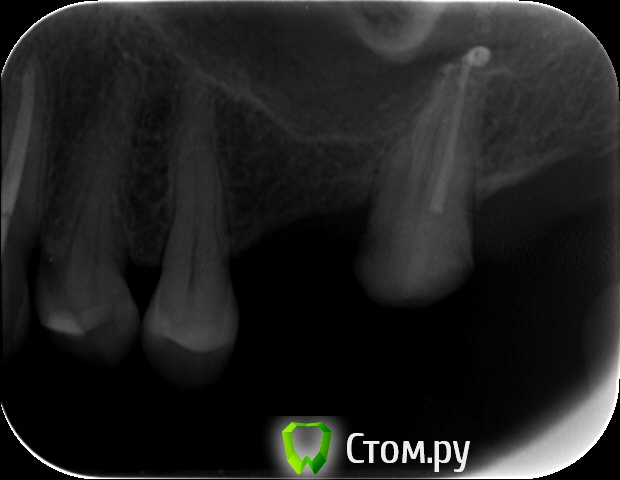

an_ver Опубликовано 29 мая, 2014 Поделиться Опубликовано 29 мая, 2014 Закрытый синус.Набор SCA.SPI 3,75*10 мм 5 Ссылка на комментарий

NickN Опубликовано 29 мая, 2014 Поделиться Опубликовано 29 мая, 2014 Закрытый синус.Набор SCA.SPI 3,75*10 ммНа снимке насадка SCA один в один к МИСовском наборе для компрессии)) Какой графт использовали? Ссылка на комментарий

zzkz Опубликовано 30 мая, 2014 Поделиться Опубликовано 30 мая, 2014 1. Сколько в итоге подняли?2. Имплант какой длины?3. У Вас Rg в кабинете стоит? Ссылка на комментарий

an_ver Опубликовано 30 мая, 2014 Автор Поделиться Опубликовано 30 мая, 2014 1. Сколько в итоге подняли?2. Имплант какой длины?3. У Вас Rg в кабинете стоит?1. 4 мм 2.3,75*10 мм SPI 3.Rg да,в каждом своя пушка...дорого но удобно..RVG без проводов Дигора Ссылка на комментарий